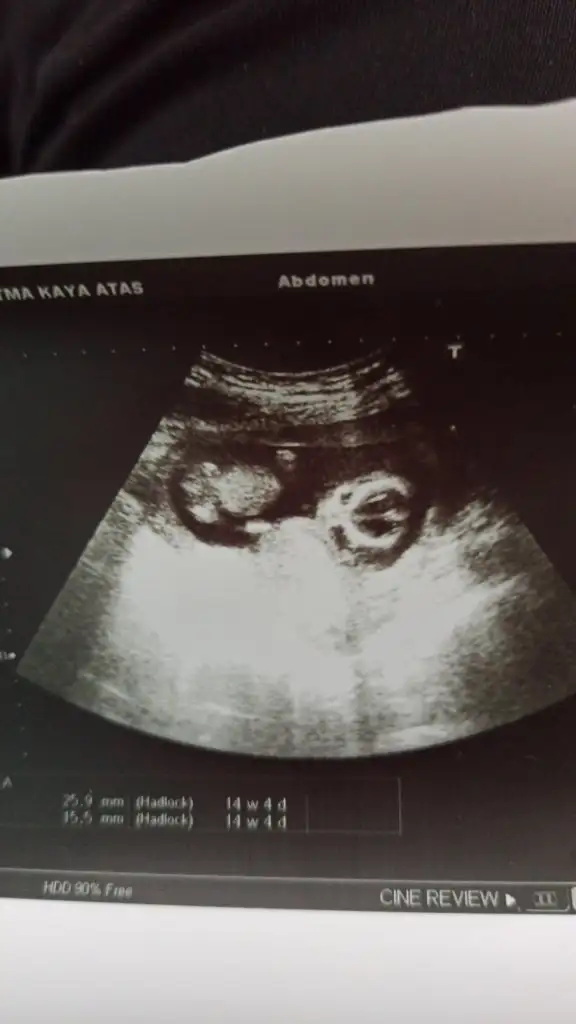

Kızlar dün kontrolüm vardı doktor %80 kız dedi bi bakar mısınız 14+2 deyiz şuan%20 oran beni biraz tereddütte bırakıyor deismz demi snradan

• IMG-20220316-WA0021.webp

15,2 KB · Görüntüleme: 112